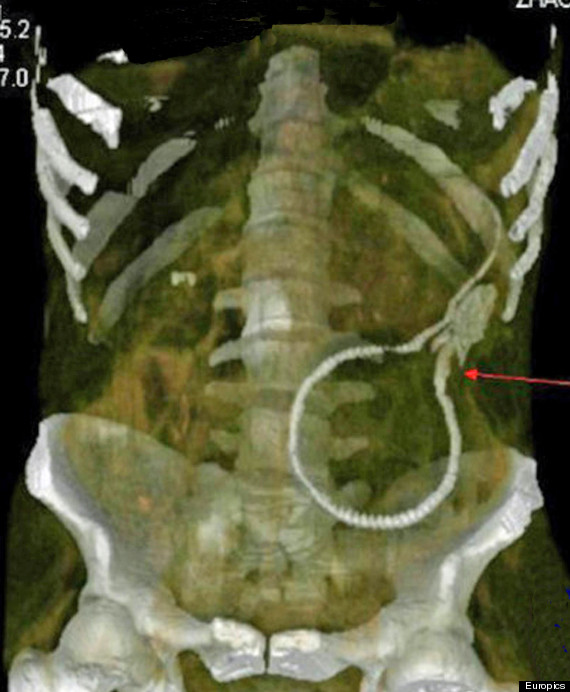

According to a HuffPost translation of Chinese news aggregation website Mop.com, the eel reportedly chewed through the man's colon, perforating his large intestine, and became stuck in his body cavity. A graphic X-ray image (seen below) shows how far inside the eel was when the man came in for treatment.

An X-ray image shows how far inside the man's body the eel was able to get.